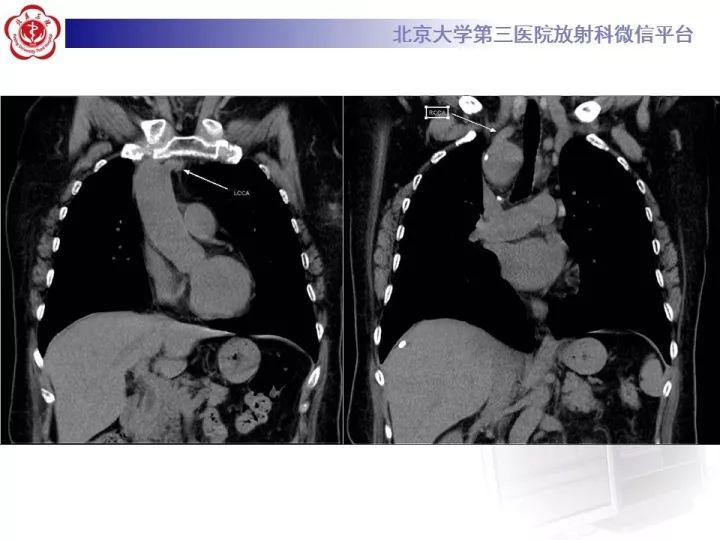

【病例】右位主动脉弓合并迷走左锁骨下动脉1例CT